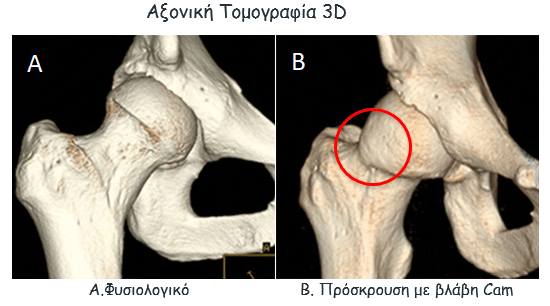

Απεικονιστικές σχολές συνδρομου μηροκοτυλιαίας διακρουσης

Η πάθηση επιβεβαιώνεται με απεικονιστικό έλεγχο. Αυτός περιλαμβάνει:

- αξονική τομογραφία με ανασύνθεση εικόνων και 3D